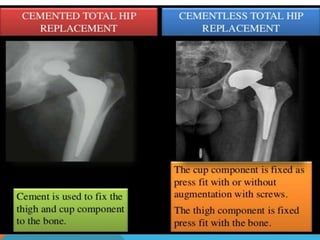

Cemented: bonds bone to bone

Can become loose and require revision

Cementless: long-term stability

Patient with high activity level and life expectancy

>25 years

Biologic fixation relies on growth of bone into the

surface

Risks for both:

Infection

Clots

Joint breakdown